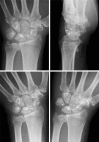

Palmar-divergent dislocation of the scaphoid and the lunate

We describe a patient with palmar-divergent dislocation of the scaphoid and lunate. After successful closed reduction, the scapholunate and lunotriquetral ligaments were sutured through the dorsal approach, and the anterior capsule was sutured through the palmar approach. The scapholunate and lunotriquetral joints were fixed with Kirschner wires for 7 weeks. At the 1-year follow-up, magnetic resonance imaging showed no evidence of avascular necrosis of the scaphoid or lunate, and radiographs showed no evidence of the dorsal and volar intercalated segment instability patterns associated with carpal instability. However, flexion of the scaphoid and a break in Gilula's line remained. To our knowledge, this is the first report showing treatment of palmar-divergent dislocation of the scaphoid and lunate by suturing the carpal interosseous ligaments.